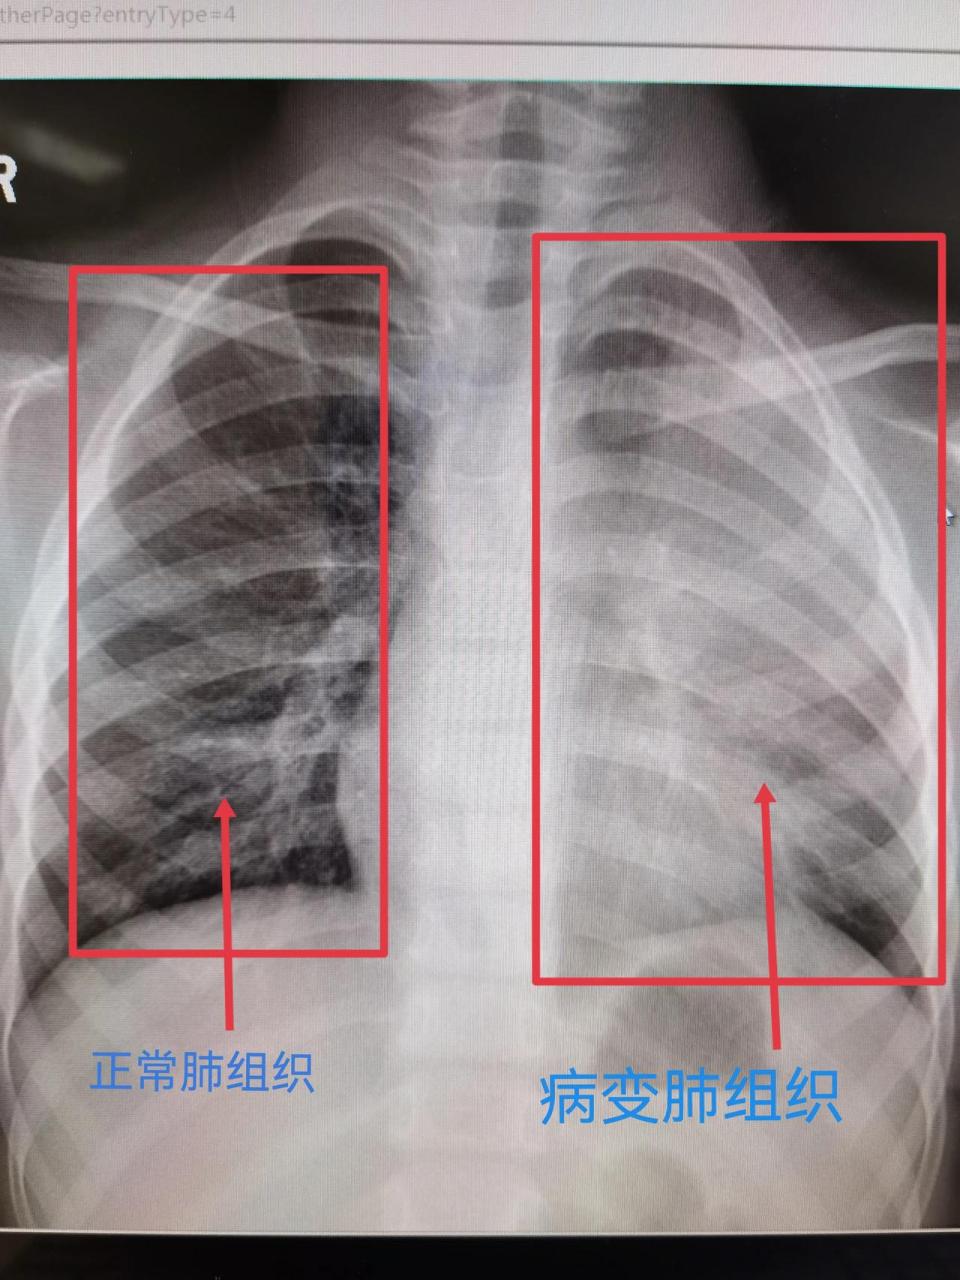

超详细胸片教学不信你还学不会

像这种情况,靠自身免疫力自愈或者门急诊口服药治疗都是行不通的.